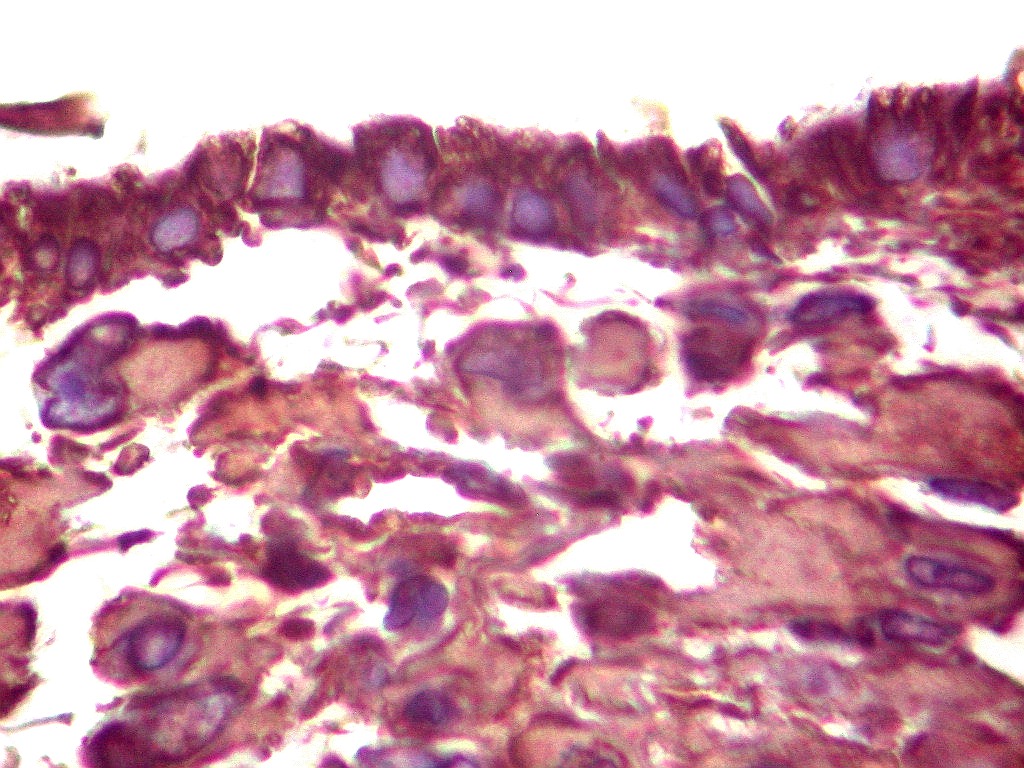

Tumor teratóide rabdóide atípico de III ventrículo.

GFAP.     O filamento intermediário do citoesqueleto que caracteriza os astrócitos é forte e difusamente positivo nas células neoplásicas deste tumor teratóide-rabdóide atípico.  Indica diferenciação astrocitária no tumor.  O folículo linfóide e vasos proliferados são negativos.  O epêndima  do III ventrículo, onde o tumor está localizado, também é GFAP positivo.